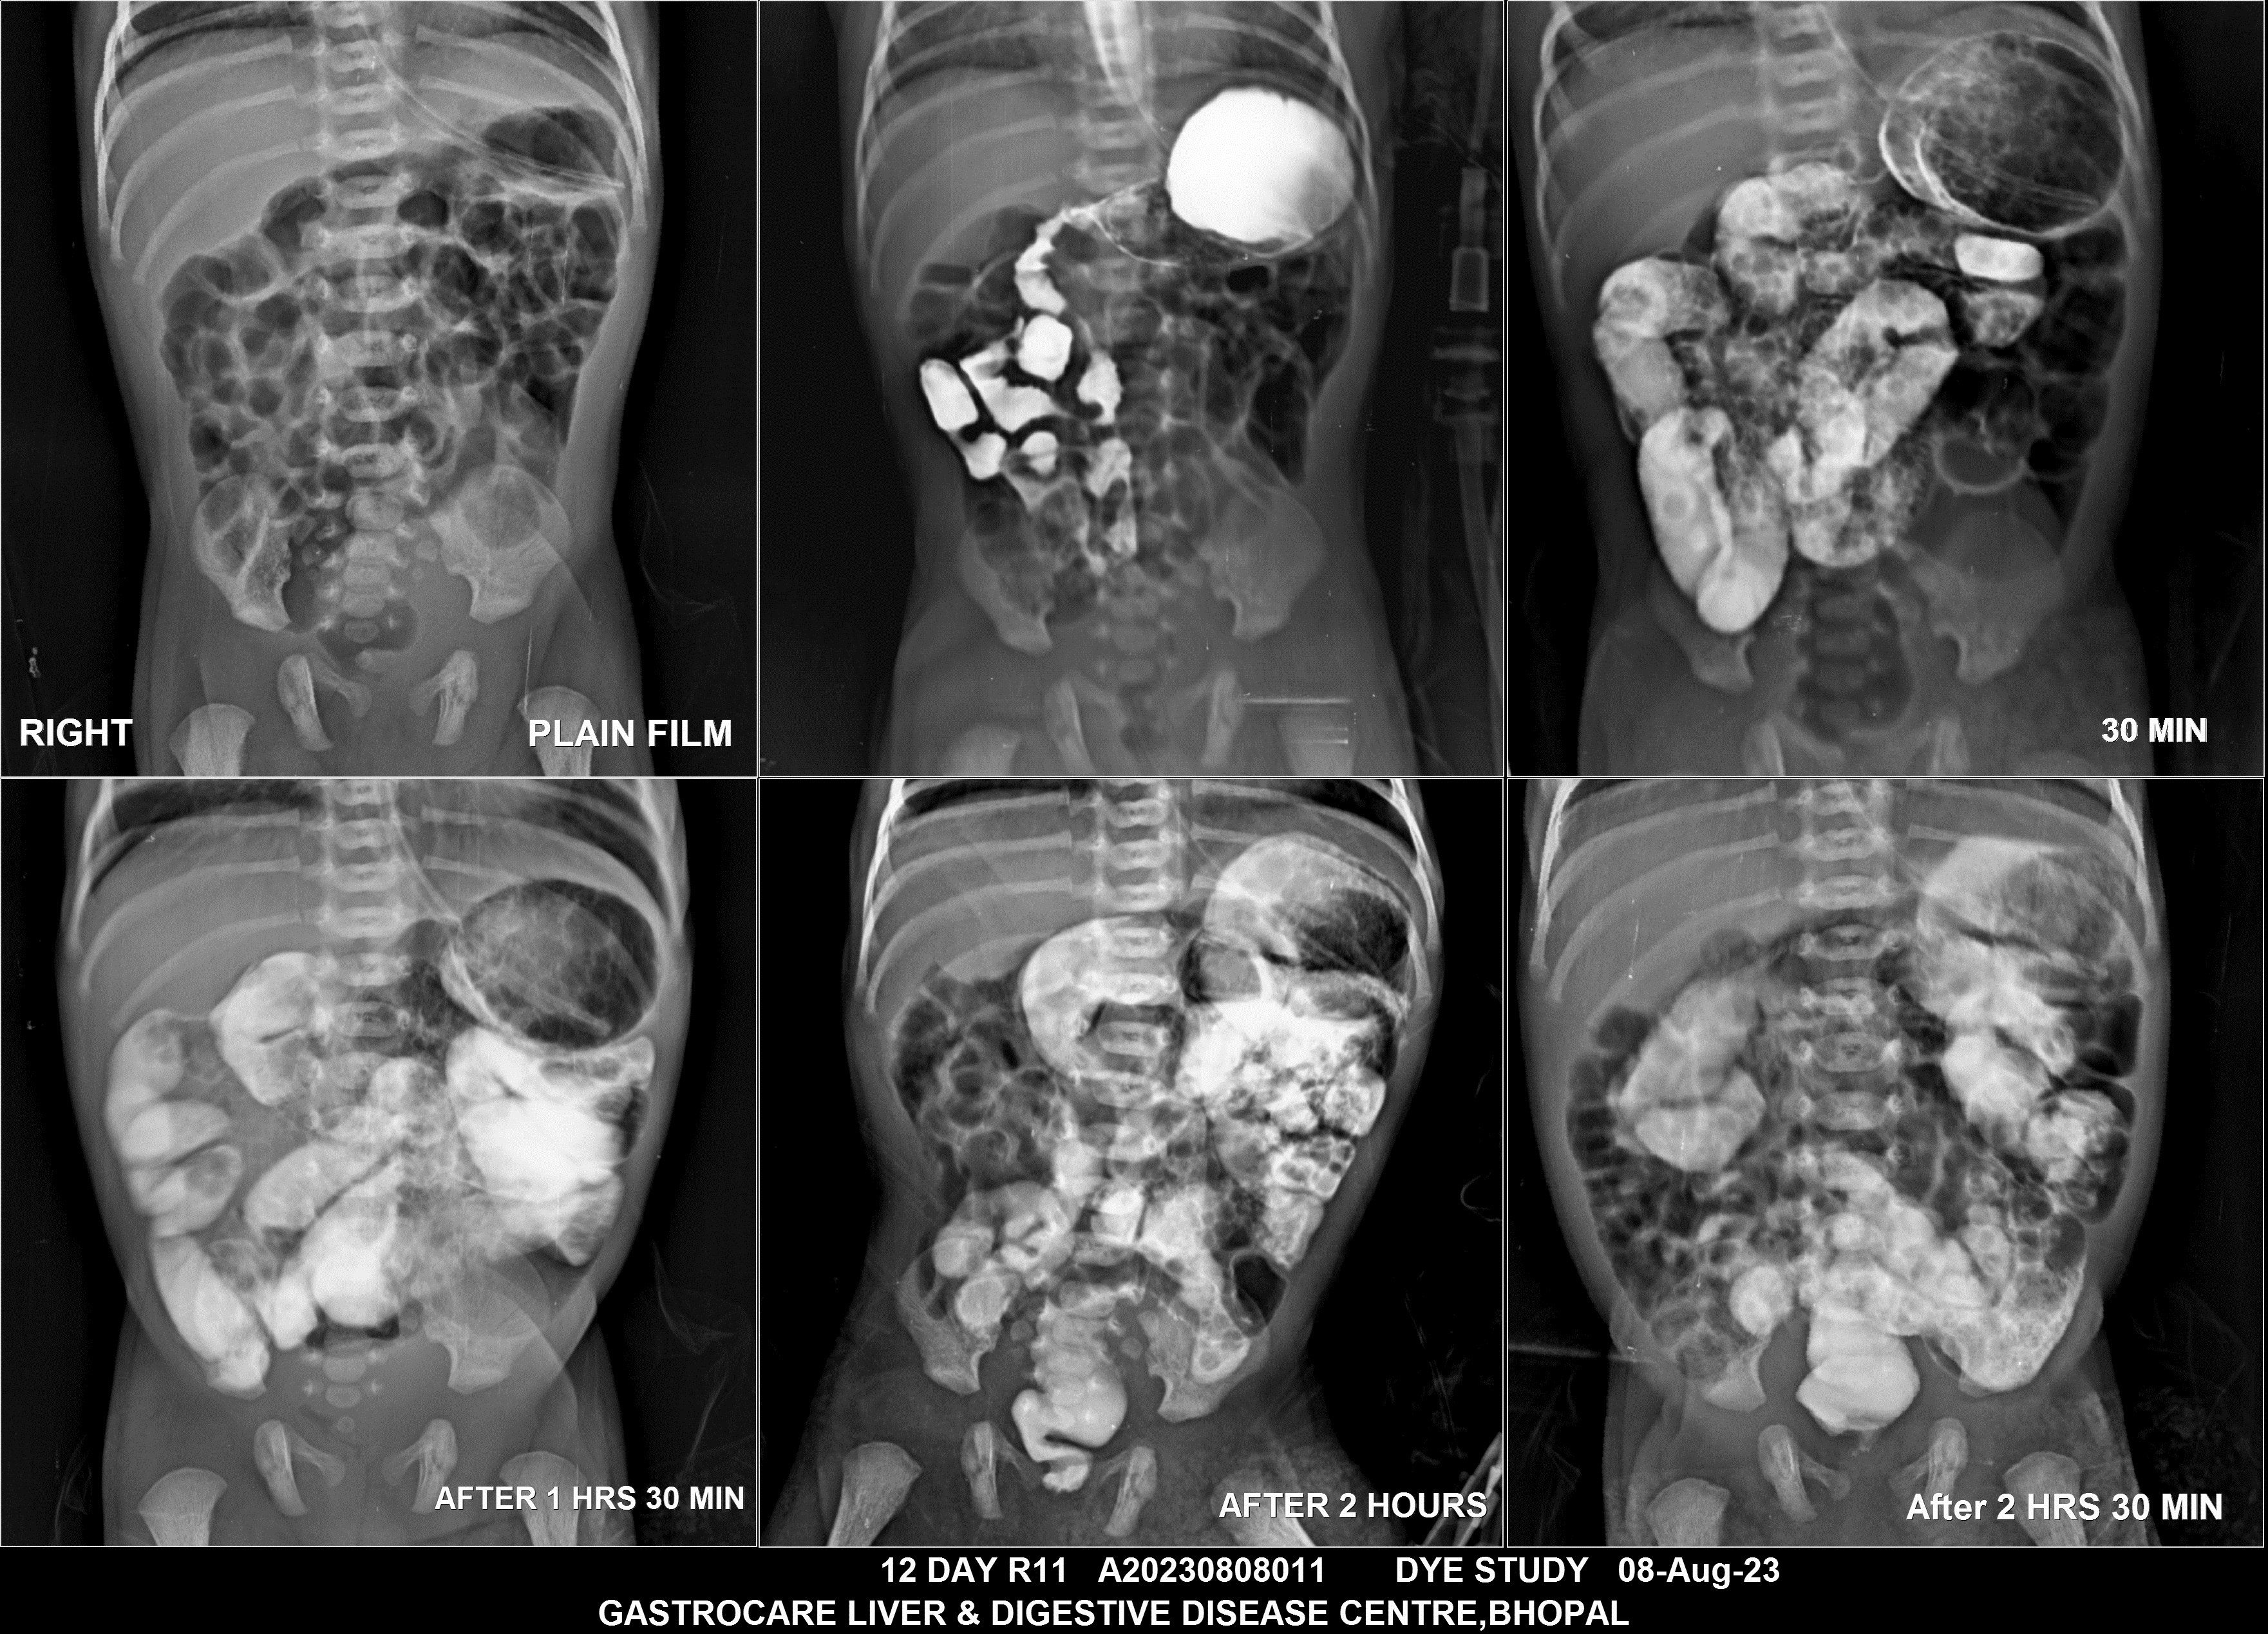

Section: BAM Total: 43 images

BaM Enteroclysis Loopogram BaE Fistulogram Urethrogram HSG